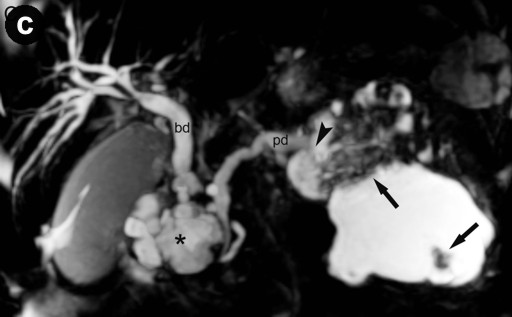

MRI (Signa EchoSpeed EXCITE HD, 1.5 Tesla, GE Healthcare, Waukesha, WI, U.S.A.) was performed and showed two mainly cystic tumors in the pancreatic head and tail with low intensity in T1-weighted images and high intensity in T2-weighted images. The intracystic solid tumor nodules were T1 and T2 hypointense and showed an intensive early, focal gadolinium uptake on dynamic contrast-enhanced T1-weighted images (Figure 2ab). T1-weighted contrast-enhanced images, T2-weighted images, and magnetic resonance cholangiopancreatography (MRCP) clearly depicted the communication between the two separate tumors and the pancreatic duct (Figure 2c).

Figure 2. a. Axial T2-weighted image at the level of the pancreas shows the manifestation of the intraductal oncocytic papillary neoplasm in the pancreatic tail. Communication to the pancreatic duct can be identified (arrowhead) as well as the hypointense solid tumor parts (arrows). b. Axial T1-weighted image after contrast enhancement with gadolinium at the same level also shows communication to the pancreatic duct and strong enhancement of the solid tumor parts (arrows). c. MRCP clearly depicts communication of the dilated pancreatic duct (pd) with the intraductal oncocytic papillary neoplasm in the pancreatic head (asterisk) and tail (arrowhead); the solid tumor components are observable. (bd: dilated common bile duct). |